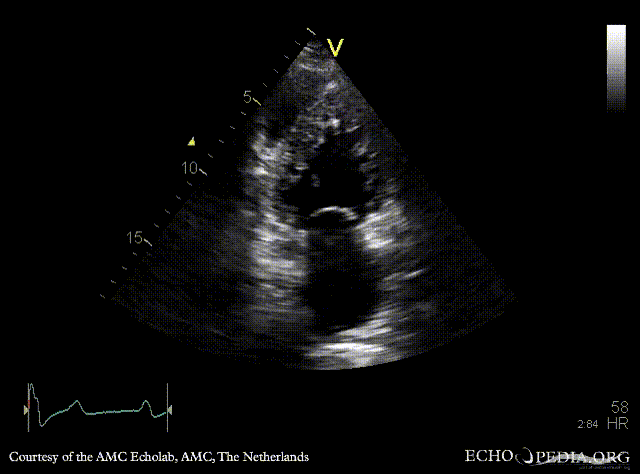

Ebstein anomaly and non-compaction cardiomyopathy

A4CH: high insertion of tricuspid valve, dilated right atrium and right ventricle, non-compaction of left ventricle A4CH with Color Doppler: severe tricuspid regurgitation